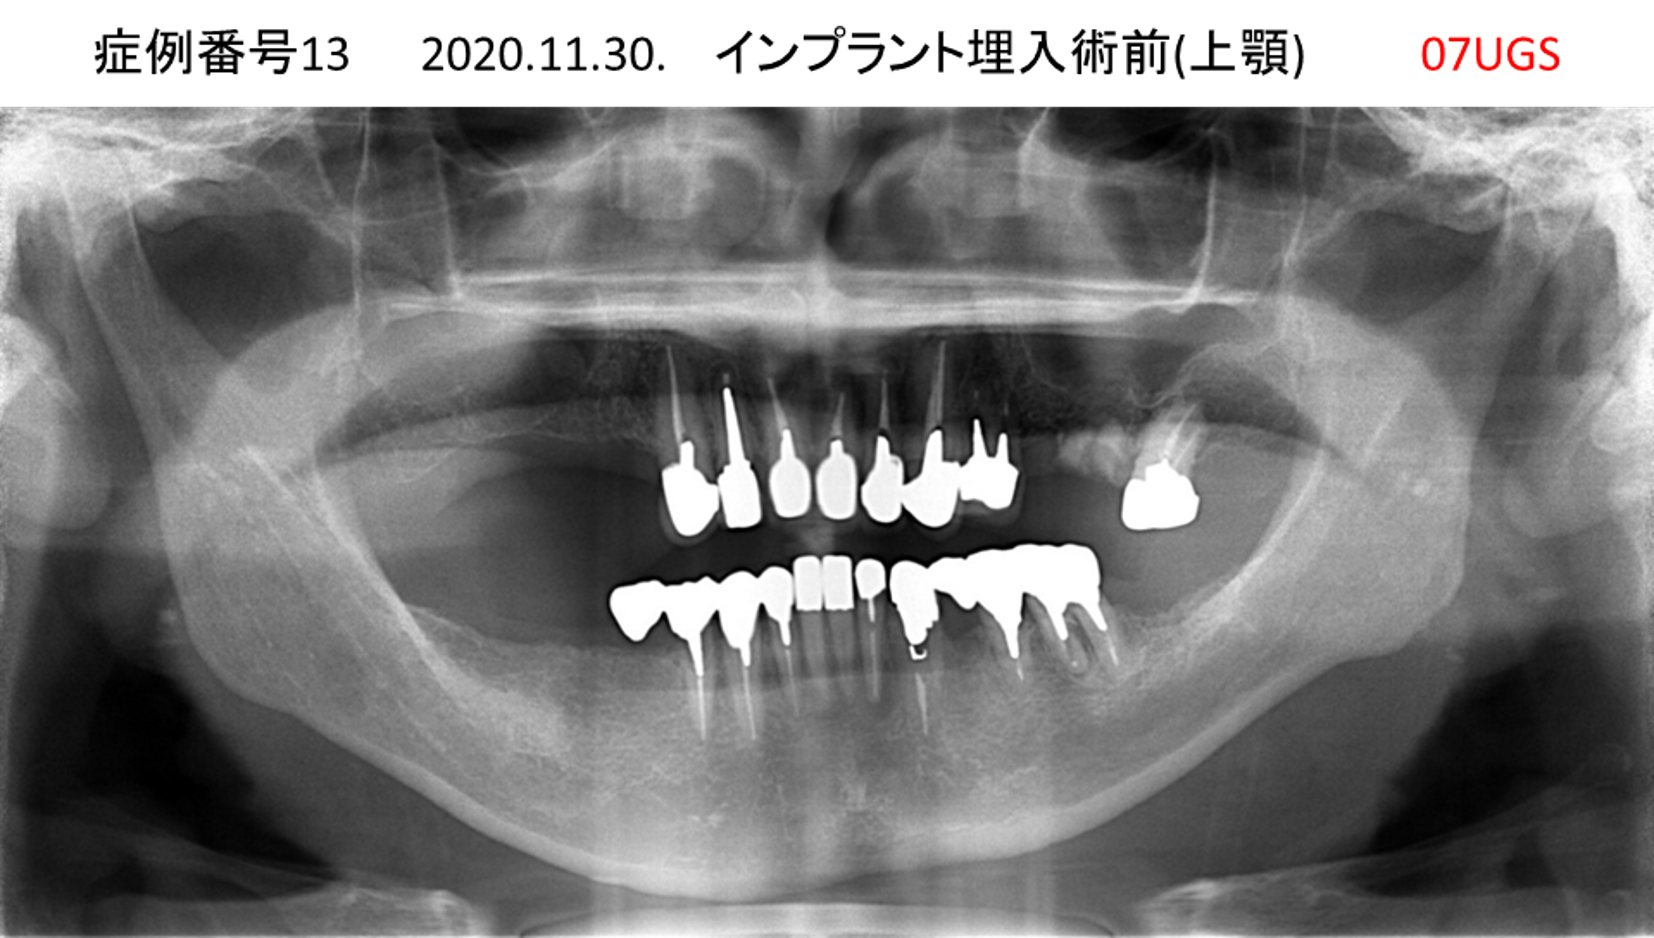

全く噛めない患者様のインプラント症例

| 治療名称 |

インプラントAGC |

| 治療費用 |

860万円+税 |

| 治療期間 |

12か月 |

| 患者さんの症状(主訴) |

全く噛めない、ごはんが後もに食べられるようになりたい、人前で口元を隠したくない |

| 治療内容 |

サイナスリフト、GBR、インプラント、AGC |

| 治療結果 |

しっかり噛めて踏ん張ることができる。食べ物をを選ばなくて済む、何でも食べられる、体重が増えた。見栄えがきれいすぎて自分じゃないみたい |

| 治療の注意点(リスク/副作用) |

インプラントが壊れたら再治療が必要 |